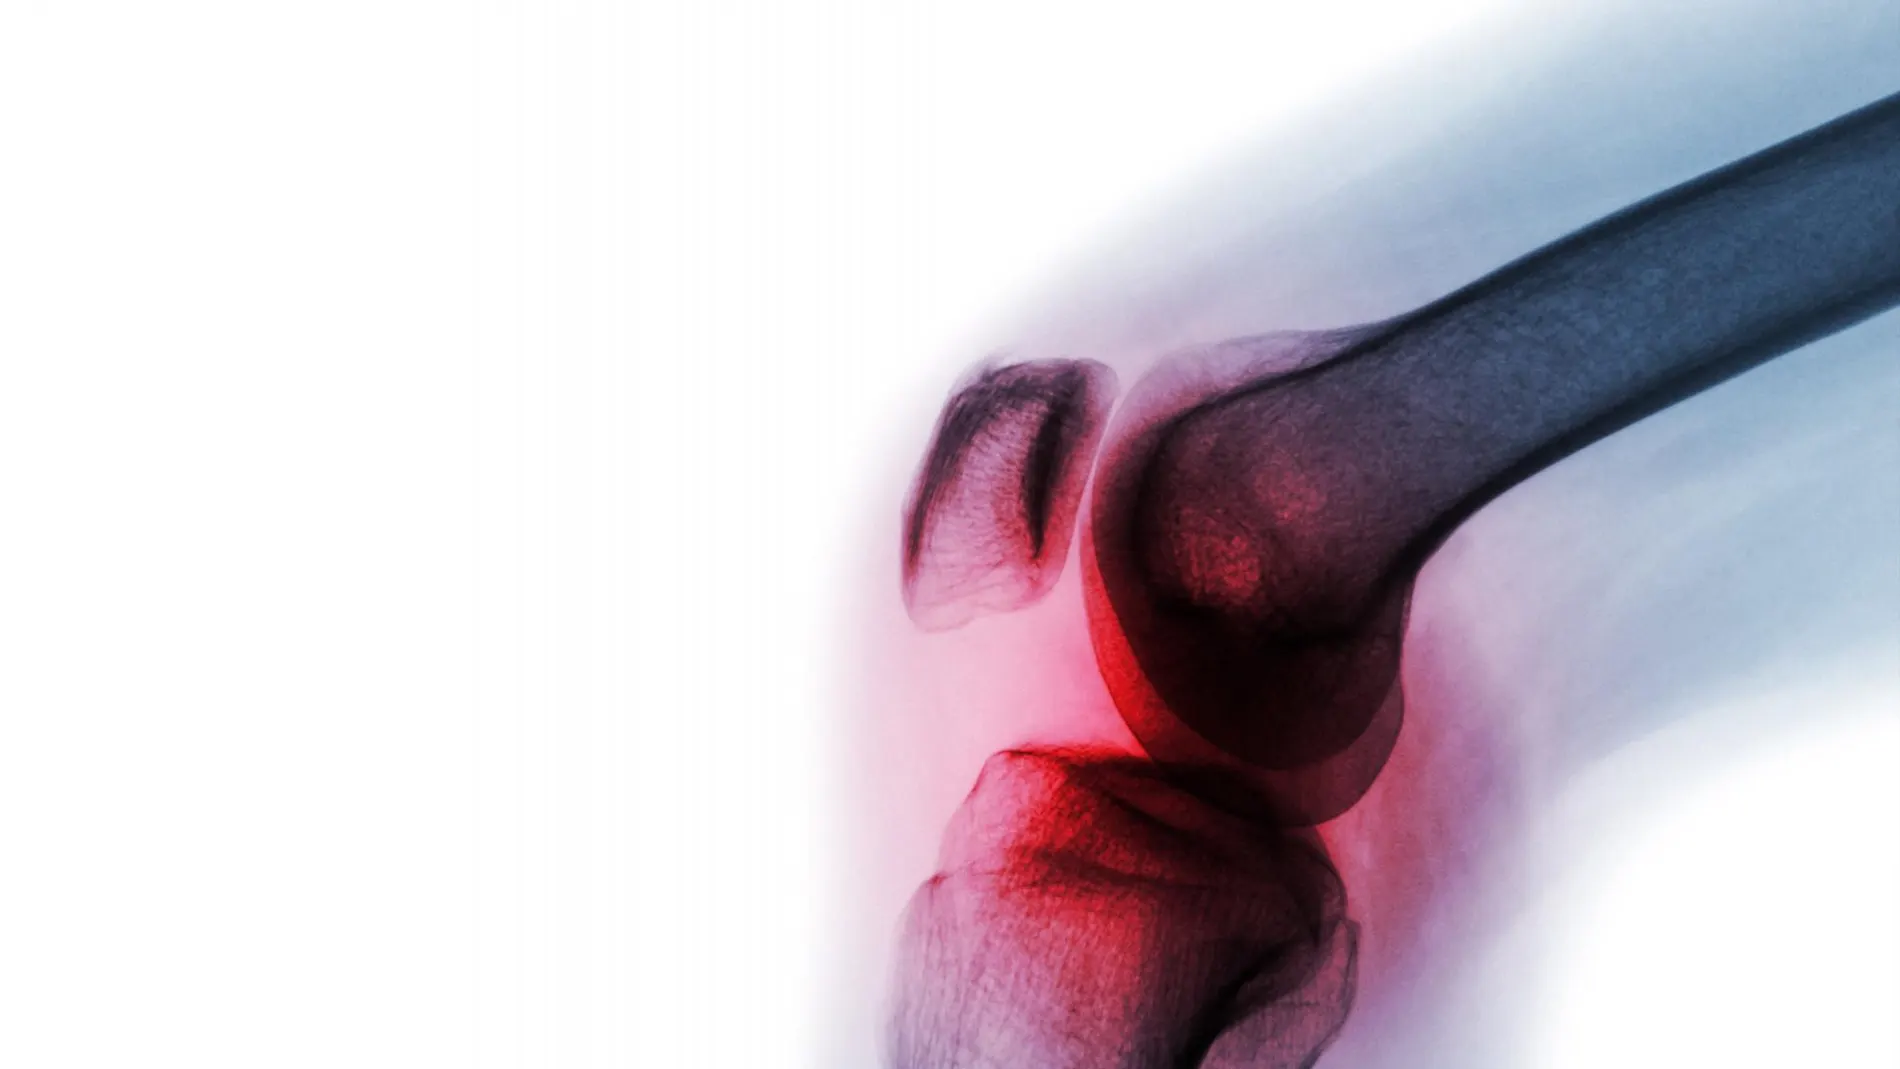

La artritis reumatoide es un trastorno inflamatorio autoinmunitario crónico que puede conllevar graves problemas de salud. Se estima que afecta al 1% de la población a nivel mundial. Entre sus principales consecuencias se encuentra la hinchazón de las articulaciones y dolor en las mismas. No obstante, también puede afectar a otros órganos del cuerpo como la piel, los ojos, los pulmones, el corazón o los vasos sanguíneos.